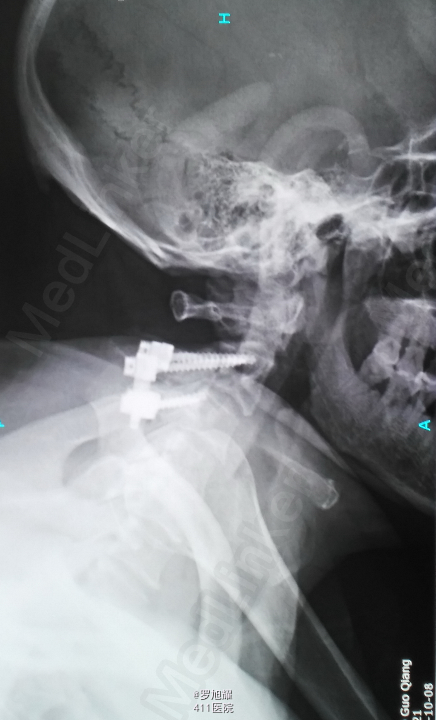

入院立即给与大剂量甲强龙冲击治疗,辅以甘露醇脱水消肿,兰索拉唑保护胃黏膜,腺苷钴胺恩经复营养神经,伤后10天复查MRI脊髓信号增高明显,两周后生命体征稳定,肢体感觉和肌力见部分恢复,行颈2椎弓根螺钉、颈3侧块钉内固定术,因神经压迫不明显未行椎板切除减压。 术后3月骨折线基本消失,患者感觉肌力几乎完全正常,右肩残留疼痛磁共振检查发现肩袖损伤,暂予局封治疗症状缓解。

该患者术后4月随访瘫痪症状完全消失,感觉正常,右侧肌力已经接近5级,但Mri随访T2加权像仍可见明显的脊髓高信号,但是影像学上脊髓变性和患者的症状没有明显的相关性,说明神经功能的代偿潜能还是非常巨大的,各位老师和同仁是否同意呢?